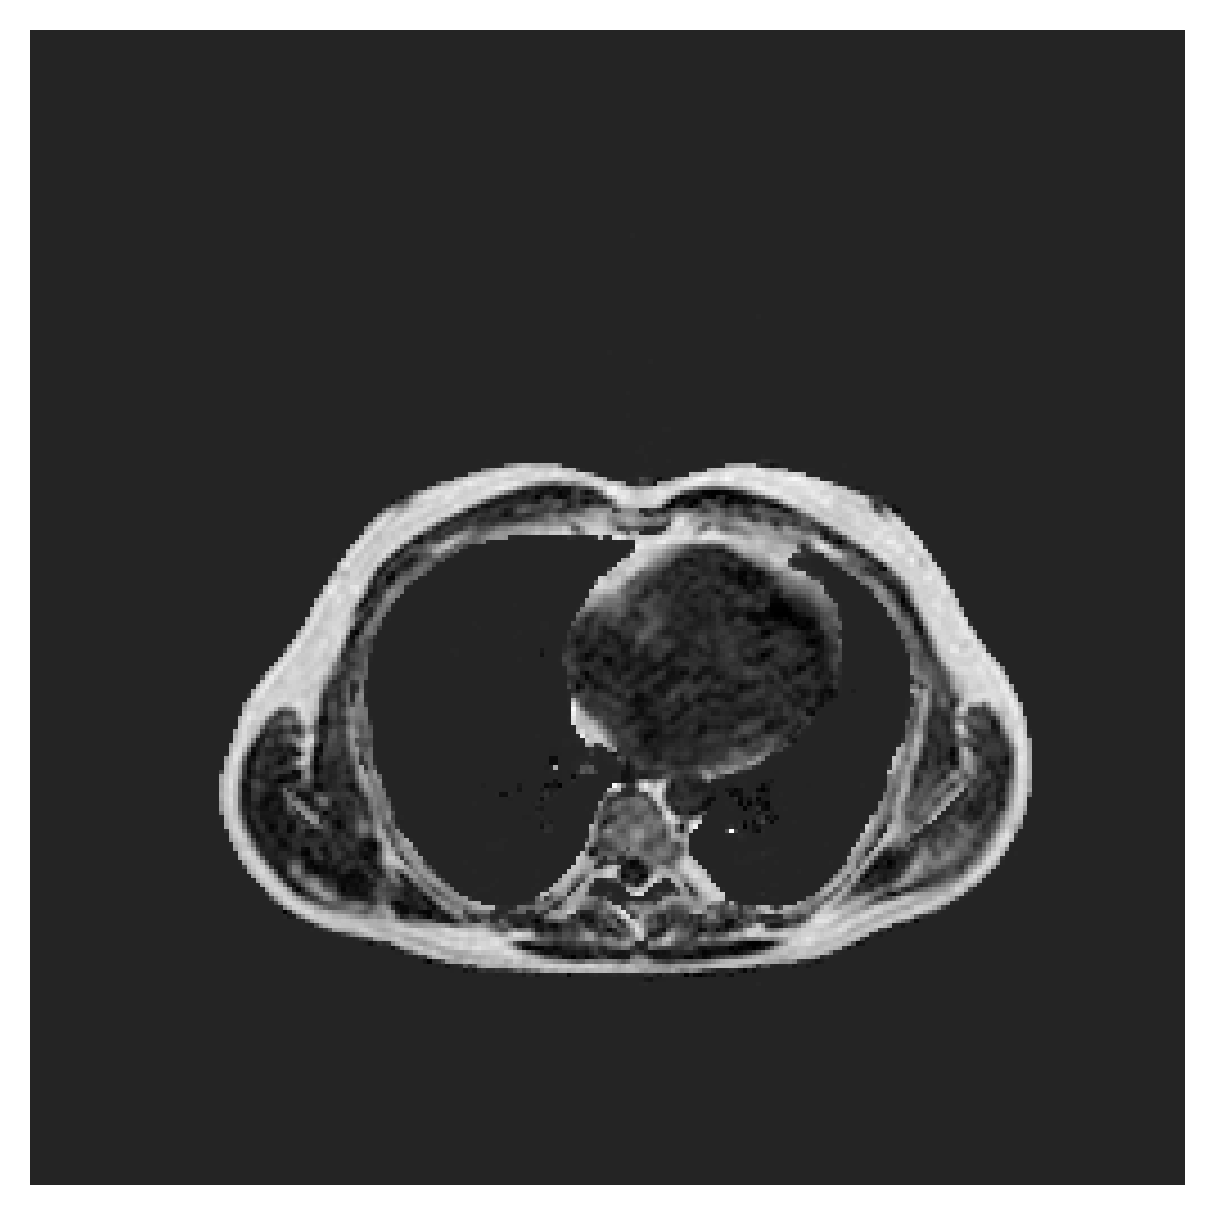

ACDC

([5]) The Automated Cardiac Diagnosis Challenge (ACDC) is a public benchmark multi-class heart segmentation dataset. It contains cine-MR images of 150 patients (of which 100 are available for training and the rest 50 comprise a test set), covering healthy scans and four types of pathologies in equal amounts, with annotations for the right ventricle (RV), myocardium (Myo) and left ventricle (LV) heart structures. We split the training set randomly, using 65 subjects for training, 10 for validation and 25 as a hold-out test set. Due to the large and varying interslice gap, we work with 2D slices instead of 3D volumes directly. This includes distance map computation.

We normalize the volumes and resize the slices to pixels. As the official dataset comes with full annotations, we create a synthetic point ground truth. This is done by first randomly choosing the centers of the point annotations within the class masks, followed by filling an ellipse with axes lengths of and (in pixels) around each center. The intersections of these elliptic discs with the underlying full annotations are then used as our point ground truth. See Figure 2 for an example of the created weak annotation mask. The point annotations are created for every slice, one for each foreground object present in the slice.